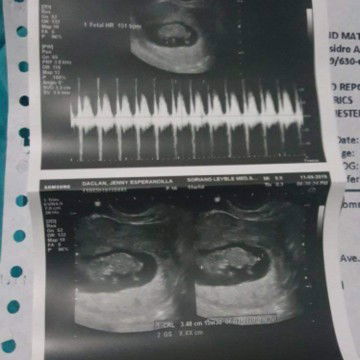

My first baby ? 11 weeks ❤️ Thank you Lord??

First time mommy